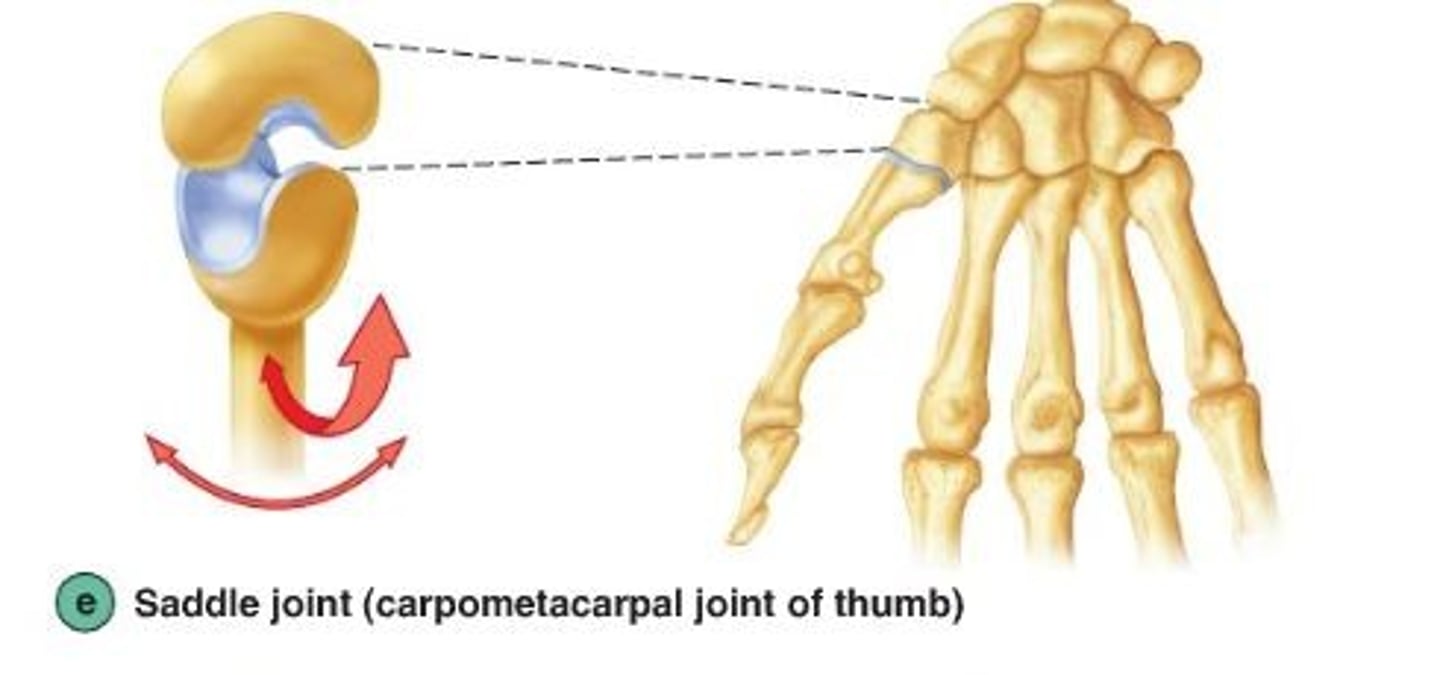

Art. Sellaris

Divasu seglveida

Art. Sellaris

Art. carpometacarpalis pollicis